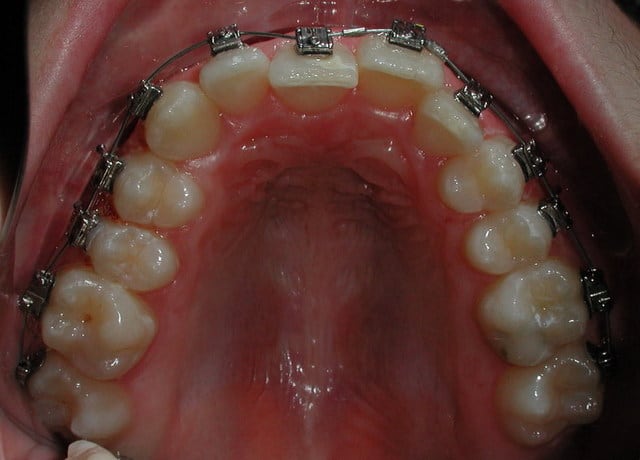

vue occlusale

Capturer 2 2 ftamlv - Eugenol